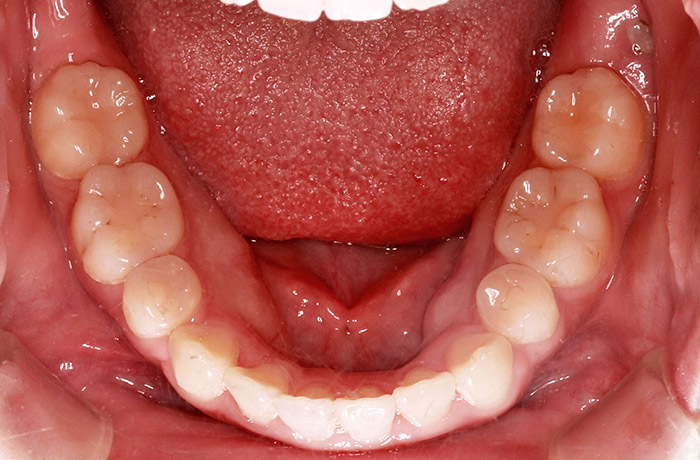

治療前

before

患者の症状 上顎前歯の前突、開咬、下顎前歯部の空隙

治療方法 非抜歯で、マウスピース型カスタムメイド矯正歯科装置による矯正

上顎臼歯の遠心移動とIPR(歯間隣接面を削合)しました。

治療結果 上顎前歯の前突、開咬が改善されました。